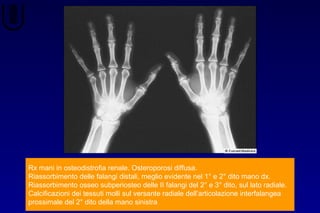

Rx mani in osteodistrofia renale. Osteroporosi diffusa.

Riassorbimento delle falangi distali, meglio evidente nel 1° e 2° dito mano dx.

Riassorbimento osseo subperiosteo delle II falangi del 2° e 3° dito, sul lato radiale.

Calcificazioni dei tessuti molli sul versante radiale dell’articolazione interfalangea

prossimale del 2° dito della mano sinistra